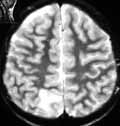

2. Подострый период (Рис. 2).

• изоденсивный очаг (1-3 недели) может быть обнаружен по косвенным признакам (масс-эффект + сглаженность прилежащих субарахноидальных пространств + смещение и сдавление боковых желудочков + смещение срединных структур + деформация подкорко-корковых участков в-ва

г/мозга;

• постконтрастное усиление вдоль внутренней границы очага.

• наиболее чувствительная методика в этом периоде из-за высокой чувствительности Т-1 режима к продуктам организации крови (метгемоглобин);

• позволяет четко различить суб- и эпидуральные гематомы за счет выявления (при эпидуральных гематомах) по периферии выражение гипоинтенсивного ободка (твердая мозговая оболочка);

• те же косвенные признаки что и при РКТ.

Рис. 2. Субдуральная гематома в проекции верхне-латеральных отделов правой лобно-теменной области. Подострая стадия. Т1 режим